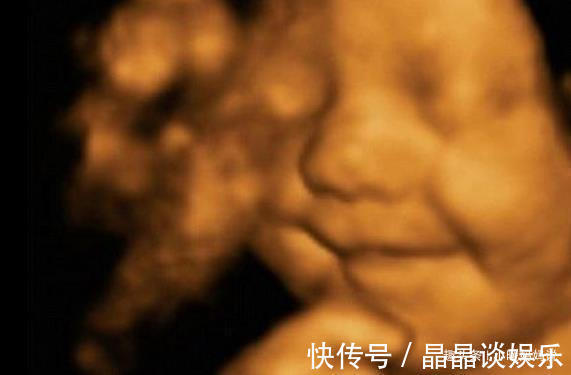

快来看看更多9个月大宝宝在肚子里的萌表情吧1. 揉眼睛这宝宝在揉眼睛,想必在肚子里待着无聊了吧,都困了,心想:“什么时候能出去,太没意思了。”2. 吃手手没想到吧,还没出生就开始吃手手了,也没有什么好吃的,只能先吃自己的小手手啦。

3. 吐舌头也不知道宝宝是不是饿了,觉得妈妈的羊水“不管饱”,都想快点出去吃上香喷喷的奶。4. 偷着乐应该是宝妈开心的情绪,他也感受到了,在妈妈肚子里偷偷的笑,这么小就会“捡笑话。”5. 瞪眼睛天天看见的都是一样的东西,真想看看外面的世界,瞪大眼睛试试吧。

4. 玩脐带这是最让人头疼的调皮宝宝,在肚子里没有意思,自己玩脐带,有的玩来玩去,就弄成“脐带绕颈”,自己打开不了吧,就会有窒息的危险。5. 各种表情宝宝在肚子里也会好奇外面的世界,也会觉得无聊,就“偷听”妈妈和别人说话,偶尔听到好笑的,自己还偷偷笑。